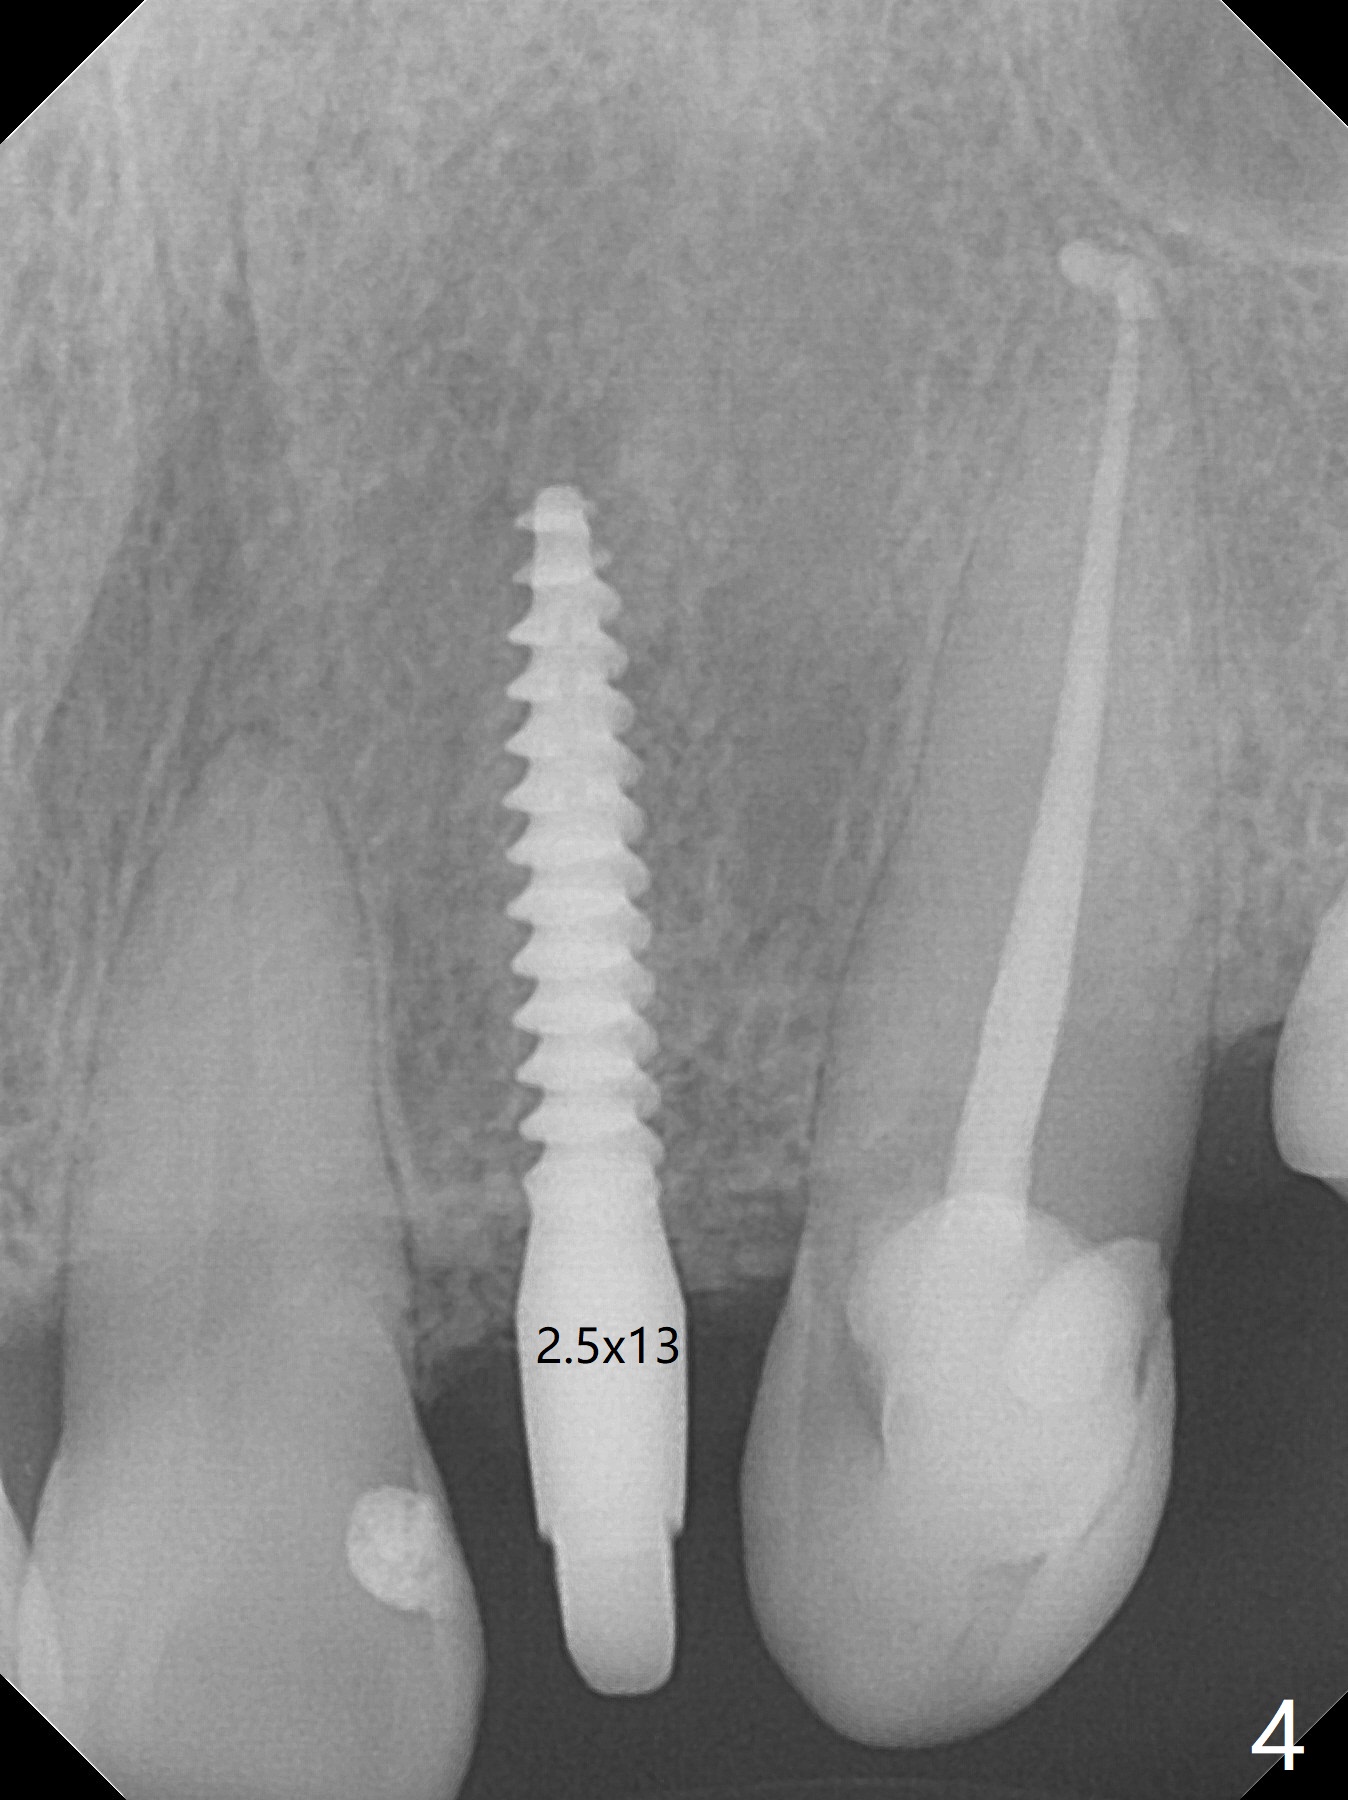

The patient has gummy smile (Fig.1).  The edentulous ridge at #10 has buccal concavity (Fig.2 *).  The surgical guide fits well without #9 distal trimming.  With 34 mg Xylocaine and 17 mcg Epinephrine infiltration at #10 and 12, the patient feels pain when 2.2 (in fact 1.9) x8.5 mm drill is being used.  When Septocaine is added, the osteotomy at #10 is found distal.  Out of curiosity, PA is taken with 2.2x10 mm drill in place; its trajectory seems satisfactory (Fig.3).  When a 2.5x13 mm 1-piece implant is placed free hand, it deviates palatal, which is confirmed with incision after addition of 34 mg Xylocaine and 34 mcg Epinephrine.  A new osteotomy is created by S-Mini Kit buccal to the previous one.  With Lindamann bur to adjust the position of the new osteotomy twice, the last drill (2.0 mm) apparently starts to perforate the apical portion of the buccal plate.  The perforation seems to enlarge when the mini implant is re-placed (Fig.4, 8 (green area) <30 Ncm).  With Vanilla graft (Fig.8 pink circles) and abutment height adjustment (Fig.4), a provisional is fabricated with occlusal clearance.  There are two reasons for failure of the surgical guide: failure to trim the tooth #9 distal (minor palatal guide displacement, Fig.5) and deflection of pointed drill and 2.2 mm drills over the hard palatal plate slope (Fig.6).  To avoid this complication, the pointed drill should be done free hand initially, after incision and obliquely (Fig.7).  The guide is placed to finish the rest of osteotomy if deem to be appropriate.